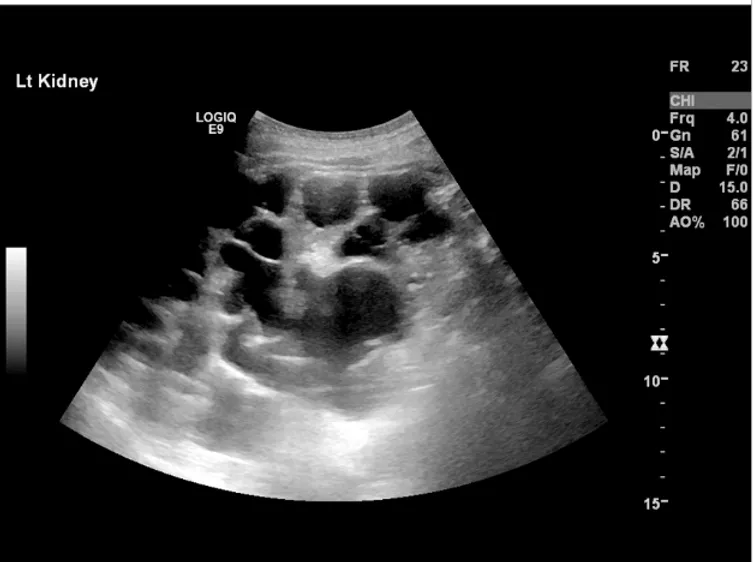

DRPAD: Muito além dos cistos! O diagnóstico da Doença Renal Policística Autossômica Dominante exige olhar atento para história familiar, achados de imagem e diagnósticos diferenciais genéticos. 📌 Atualize-se sobre os critérios diagnósticos e evite confusões com outras nefropatias císticas!